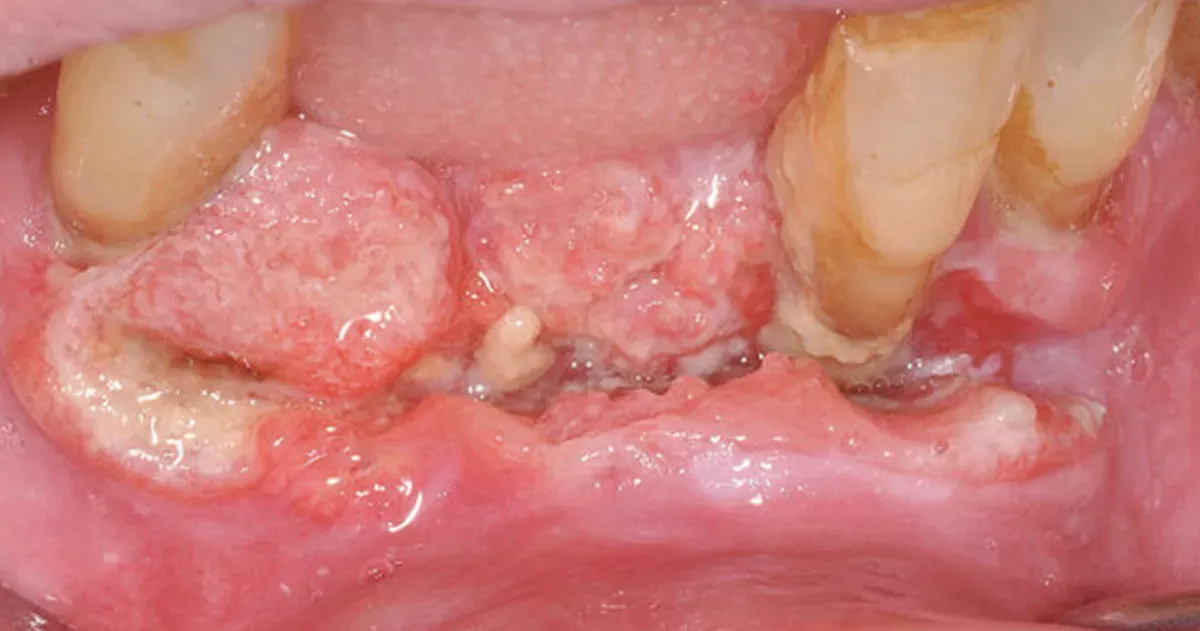

Squamous cell carcinoma

Squamous cell carcinoma is the most prevalent type of jaw cancer. It typically spreads from adjacent tissues to the jaw. In particular tumours in the gums, floor of the mouth and base of the tongue have a tendency to impact the jawbone.

A less common subtype is primary intraosseous squamous cell carcinoma, which is a rare malignancy of the jaws. The term "intraosseous" means "originating from within a bone". This type of tumour is believed to develop from the remnants of the odontogenic epithelium (dental lamina) with no initial connection to the oral mucosa.

A squamous cell carcinoma has spread from the gums to the lower jaw.